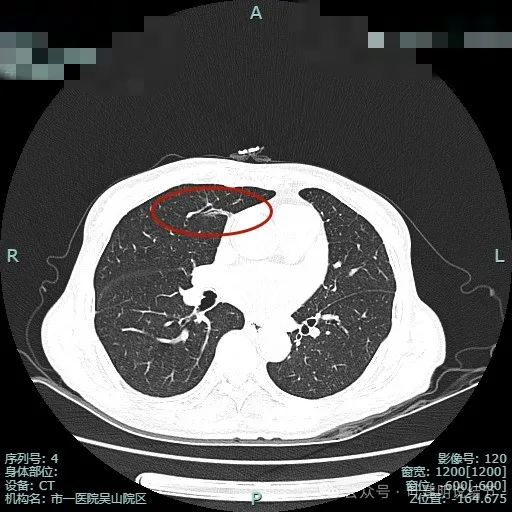

细毛刺典型而锐利;灶内有实性成分;整体轮廓清,灶内细支气管扩张通气。

上图明显感觉到收缩力,月牙铲征以及灶内细支气管扩张、锐利短细毛刺,整体轮廓与边界清,很典型恶性。